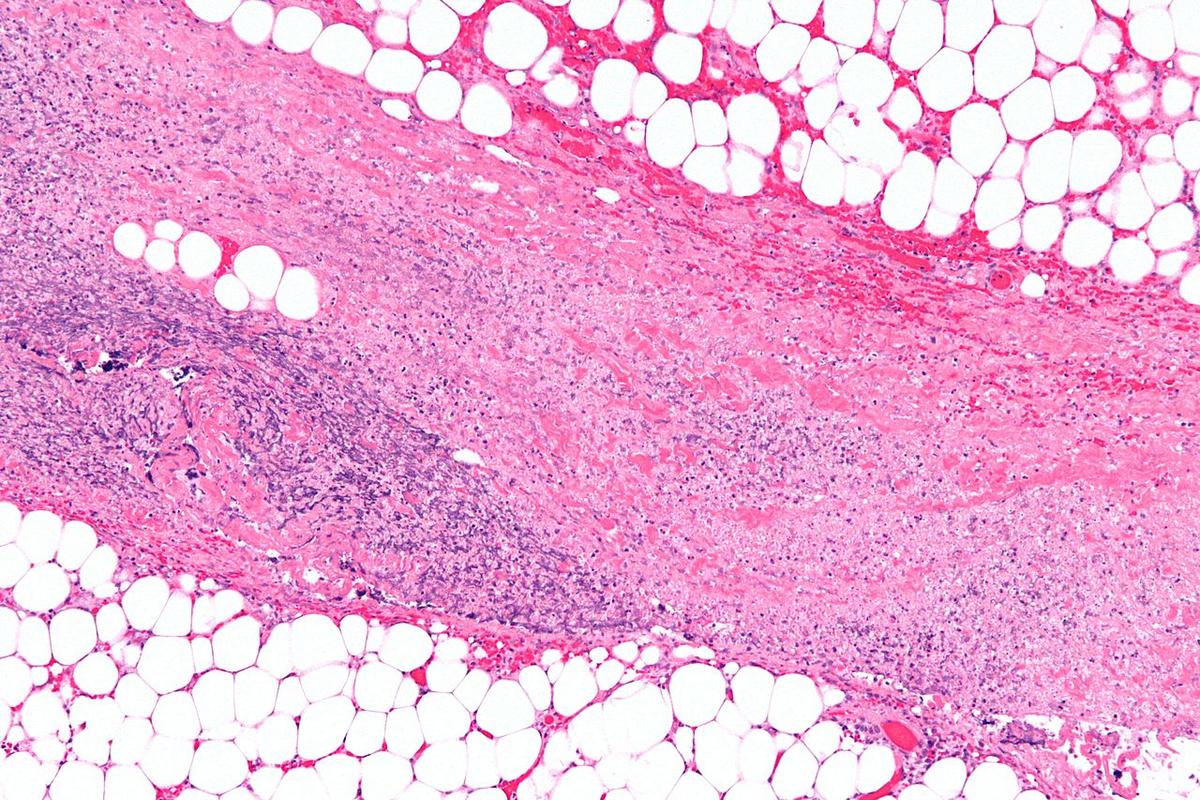

A 50-year-old Florida man has had about 25 percent of his skin removed after being stricken with potentially deadly flesh-eating bacteria.

The man has undergone three operations, which removed about 25 percent of his skin, and is scheduled for one more after contracting flesh-eating bacteria, his wife said.